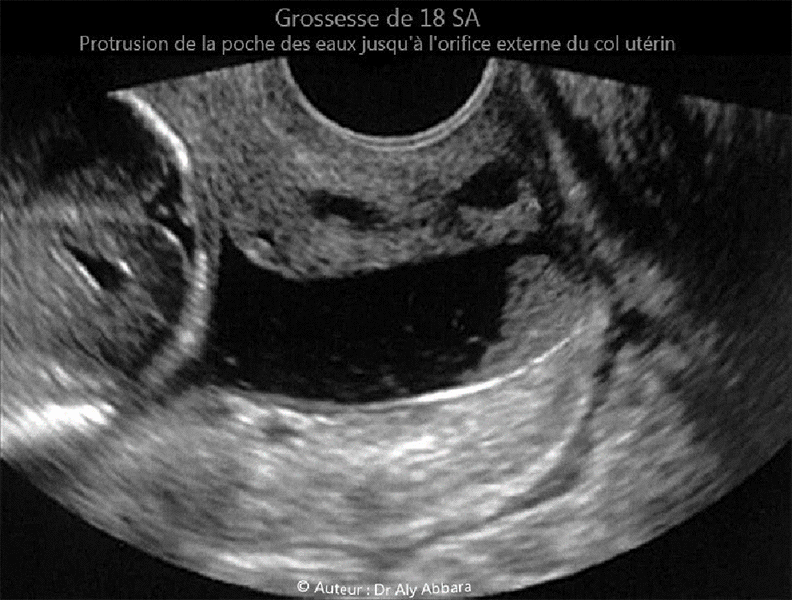

Incompétence de l'orifice interne du col utérin - Sévère menace d'avortement tardive à 18 SA - Echographie

Grossesse de 18 SA - béance du col utérin ; poche des eaux atteignant l'orifice externe du col utérin

Série d'images montrant les aspects échographiques et cliniques d'un col utérin à orifice interne incompétent permettant la protrusion de la poche des eaux dans la totalité du canal cervical pour la laisser atteindre puis dépasser l' orifice externe de col utérin qui est ouvert de 2 cm (au toucher vaginal) sur la totalité de sa longueur.

Il s'agit d'une femme enceinte de 18 SA, ayant dans ses antécédents un accouchement normal au terme de 39 SA sans aucune notion de menace d'avortement tardif ou d'accouchement prématuré lors de cette première grossesse.

Pour la 2ème grossesse en cours, cette incompétence de l'orifice interne du col utérin sévèrement menaçante d'avortement tardif fut découverte fortuitement lors d'une consultation classique prénatale à 17,5 SA, sans contractions ou douleurs abdomino-pelviennes ressenties par la patiente.

Absence de signes cliniques ou biologiques francs pouvant évoquer le diagnostic d'une chorioamniotite.

La biométrie et la morphologie fœtales sont normales ; les annexes fœtales (placenta et cordon ombilical et la quantité du liquide amniotique) sont également normales.